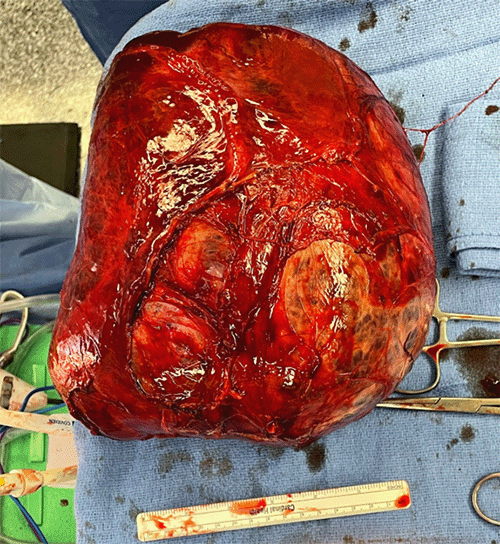

Due to the large size of the hepatic mass, an open approach was chosen for resection. The patient was placed in a supine position, and a bilateral subcostal “chevron” incision provided optimal liver exposure (Figure 4). Exploration revealed a very large right lobe hemangioma displacing the rest of the seemingly normal liver. No concerning lesions suggestive of miliary disease or metastases were identified.

Figure 4. Resected Giant Hemangioma. Published with Permission

Intraoperative ultrasound facilitated the identification and preservation of major intrahepatic structures, avoiding the need for formal liver resection.